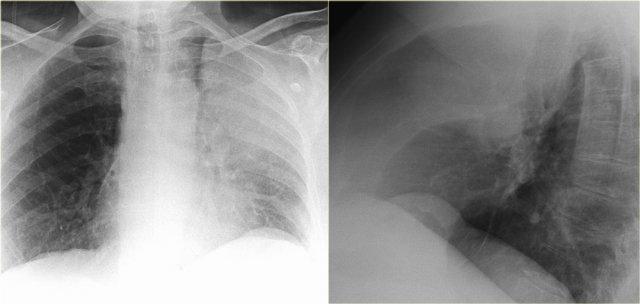

Hãy quan sát kỹ các hình X-quang trước, sau đó tiếp tục đọc.

Các dấu hiệu bao gồm:

- Đám mờ lớn bên trái kèm mất bóng tim.

- Cơ hoành trái nâng cao kèm lều hóa.

- Khe liên thùy nhỏ ở vị trí thấp

- Rốn phổi phải ở vị trí thấp

Các dấu hiệu này cho thấy xẹp hoàn toàn thùy trên phổi trái và có thể kèm xẹp một phần phổi phải.

Do bóng bờ tim phải vẫn còn nhìn thấy được, nhiều khả năng đây là xẹp một phần thùy dưới chứ không phải thùy giữa.

Tiếp tục xem PET-CT…

Ung thư phổi bên trái gây tắc nghẽn phế quản thùy trên và ung thư phổi bên phải gây tắc nghẽn thùy dưới phải.

Trên PET-CT ghi nhận khối u ở cả phổi trái lẫn phổi phải.

Bệnh nhân có nhiều di căn xương.

Một ổ di căn xương sườn được chỉ ra bằng mũi tên.

Luft sichel có nghĩa là liềm khí (mũi tên xanh dương).

Lưu ý hình ảnh phồng của khe liên thùy trên phim nghiêng.

Điều này tương tự như dấu hiệu chữ S vàng (golden-S sign) trong xẹp thùy trên phổi phải và gợi ý có khối gây tắc nghẽn ở vị trí trung tâm.